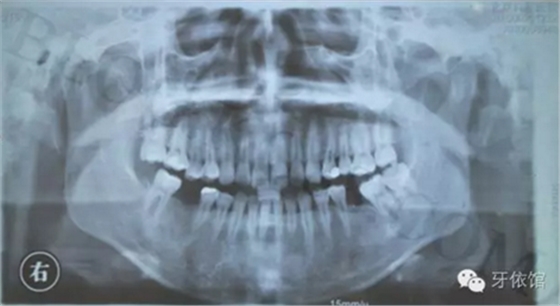

患者:女,28歲,此x光片為4年前拍的,左下6已于四年前行種植修復(fù),今天主要介紹右下6種植修復(fù)過程。計(jì)劃微創(chuàng)種植。

右下6口內(nèi)照片顯示牙槽嵴頂寬度并不是很充足,微創(chuàng)種植有一定的風(fēng)險(xiǎn),跟患者協(xié)商后,同意微創(chuàng)種植。